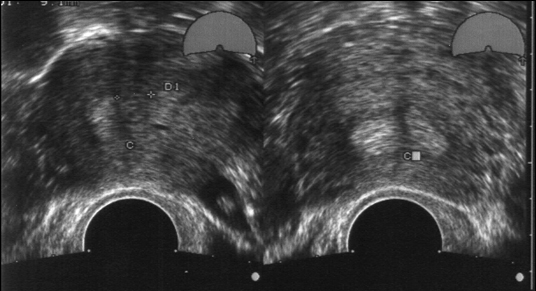

Malformation utérine. La sonde vaginale permet la réalisation de coupes transverses de l'utérus.

La seconde partie du cycle est la plus propice au diagnostic car l'endomètre échogène est le marqueur idéal